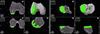

Before the end of the planning, the probe is used to map the cartilage alongside the femoral component, to confirm the component has been positioned flush with the cartilage to avoid overstuffing or understuffing. In fact, a prominent anterior tip of the femoral component can impinge on the patella during flexion, potentially leading to disease progression or pain. Cartilage mapping ensures a smooth transition from the femoral component to the anterior surface of the femoral condyle (Figure 2).

![]() |

Figure 2 Intraoperative screenshot of lateral unicompartmental knee arthroplasty using Mako® (Stryker®, Mahwah, USA), with planning modified according to Functional Positioning principles. The blue arrow indicates the points of femoral cartilage mapping, while the red arrow shows the anatomical load line of the knee, marked during the kinematic evaluation. |